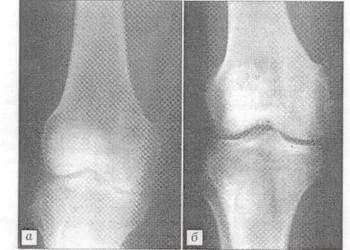

Рис.2 Рентгенограмма больной Т. 41 года.

Диагноз: воспалительный процесс в области внутреннего надмыщелка правой бедренной кости. а - после отбрытой биопсии; б - через 3 мес. после операции с пластикой дефекта "Остеоматрисом".

Анализ рентгенограмм показал, что через 1 мес. после хирургических вмешательств картина неоднороной "глыбчатой" структуры в местах заполнения дефектов "Остеоматриксом" или в пространствах между его гранулами и аллоимплантатами, выявлявшаяся сразу после опрерации, полностью исчезала. Рентгеновская ткань была практически однородной и имела умеренныю плотность (рис.1). Через 3 мес. в большинстве случаев (66%), я через 6 мес. у всех больных места, куда помещался "Остеоматрикс", по плотности рентгеновского изображения были неотличимы от окружающей губчатой костной ткани (рис. 2). Признаки перестройки замороженных кортикальных аллоимплантатов, применявшихся совместно с гранулами "Остеоматрикса", во все сроки наблюдения были минимальными (рис. 3), тогда как поверхностно-деминерализованные кортикальные аллотрансплантаты к 6-му месяцу частично инкорпорировались в материнское костное ложе (рис. 4).